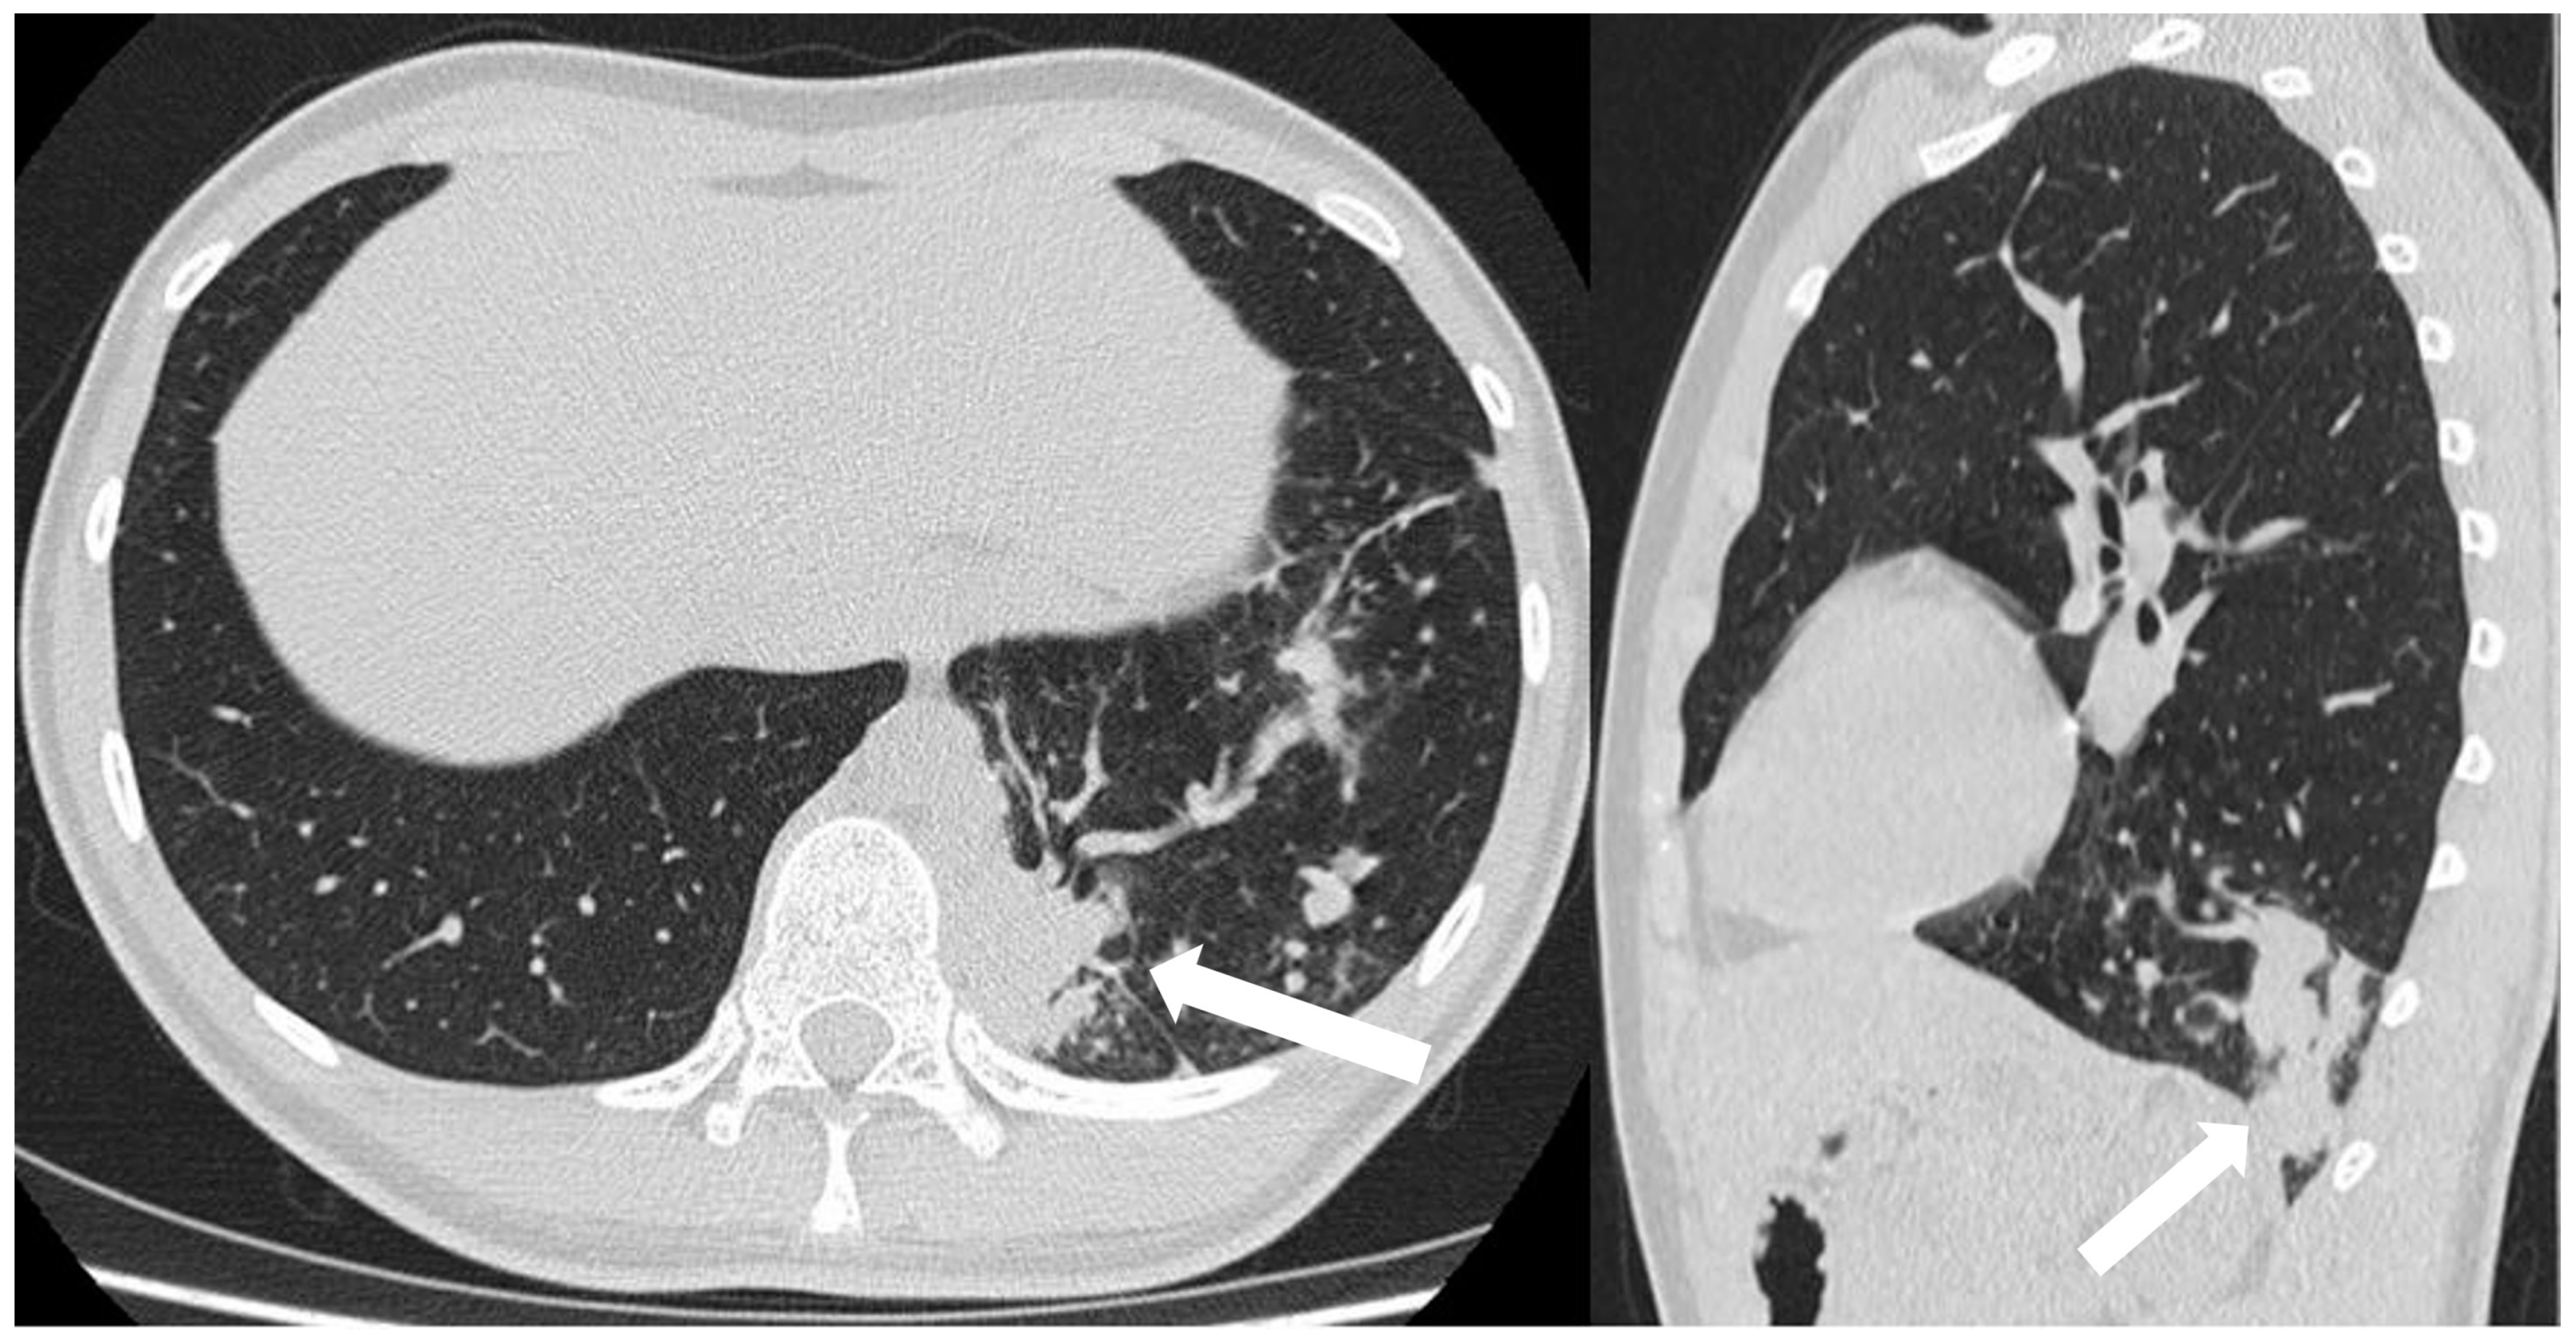

CT angiography with 3D reconstruction serves as a highly informative tool for identifying anomalous feeding arteries and drainage veins for differentiating between intra- and extra-lobar sequestration (Figure 14 and Figure 15). The CT appearance of the lesion ranges from a homogeneous soft tissue mass within the parenchyma (Figure 16) to a cystic lesion containing air or fluid, which can coexist in hybrid forms [15,37].

Figure 16.

CT scans in axial and sagittal view of a 17 year old boy with suspected intra-lobar sequestration show a homogeneous soft tissue density mass within lung parenchyma (arrows).